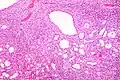

Micrograph of a cystic nephroma. H&E stain.